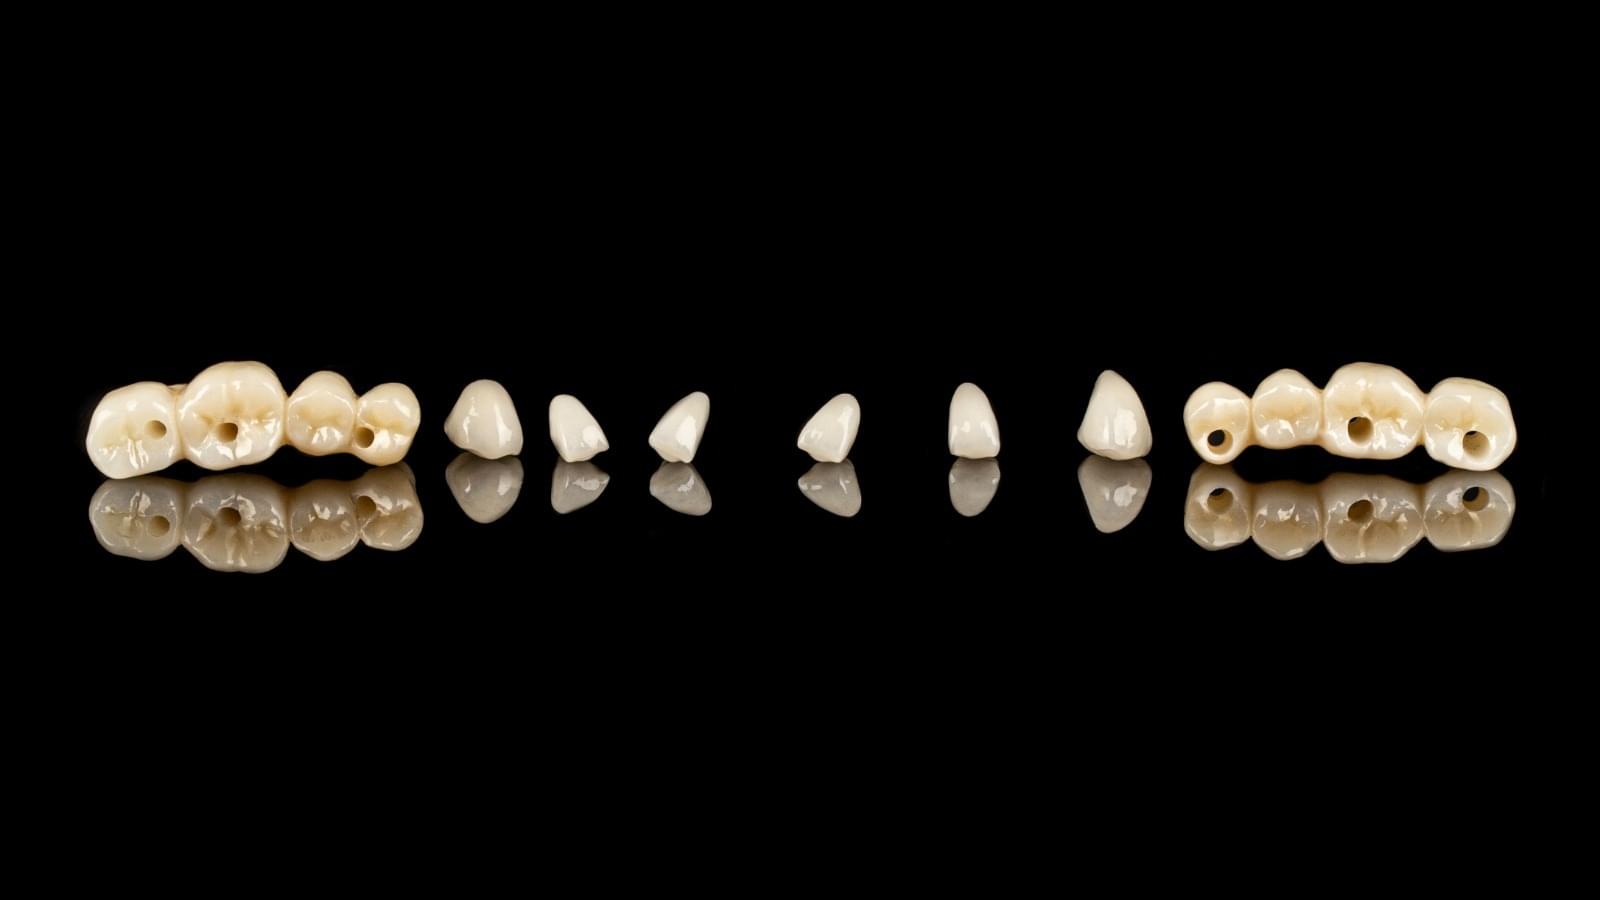

Coroană Zirconiu

PREȚ PENTRU 1 DINTE

135*

Prețurile încep de la 135€

Prin ce se deosebesc coroanele dentare din metalo-ceramică și zirconiu?

Implanturi Dentare 🔥 Cazuri finisate #1